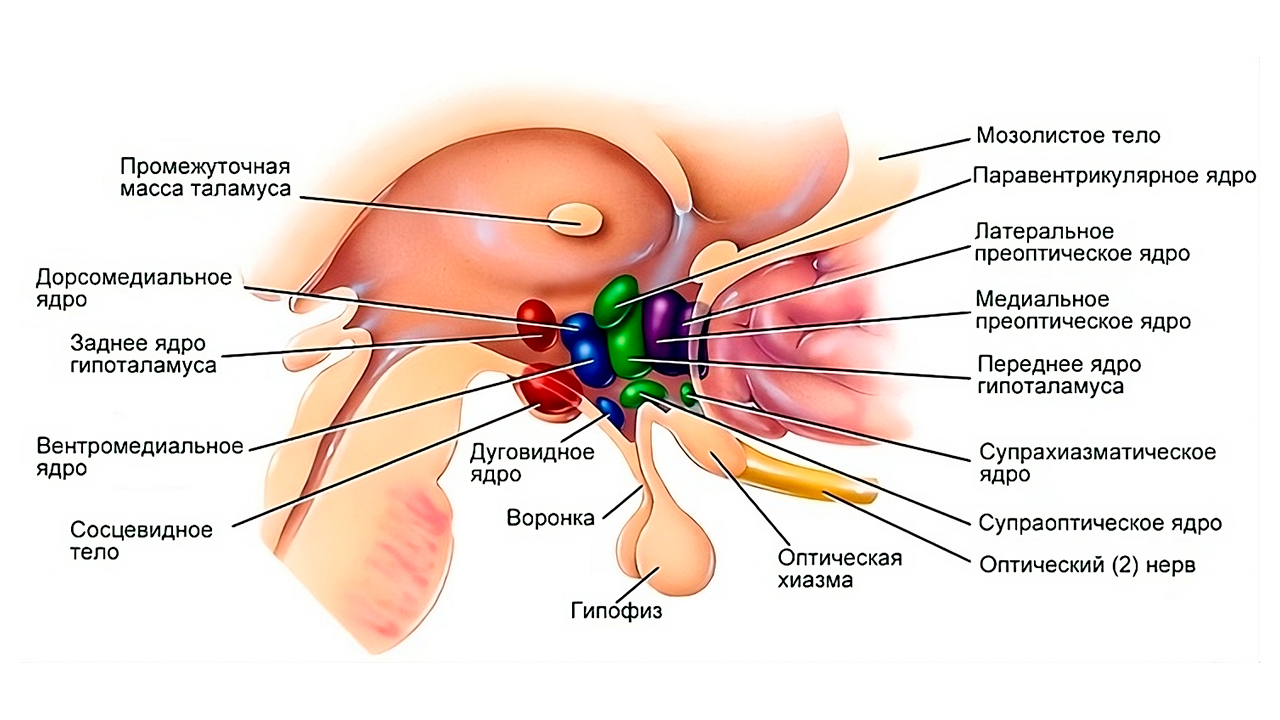

Как работает центр насыщения в гипоталамусе: визуальные иллюстрации